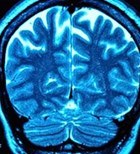

שני מקרים קשים של "אמבה אוכלת מוח" בחודש האחרון, אחד מהם...

ניתן לחיות עד 120 עם מפרצת מוחית, מבלי שהמפרצת תדמם. עם...

עלייה במקרי דלקת קרום המוח בעקבות הידבקות בחיידק מנינגוקוק...